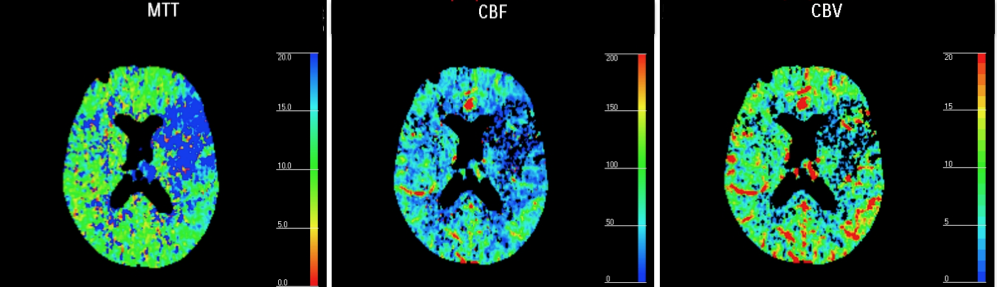

Tras aplicar los ROI, el software de la estación de trabajo nos va a dar un mapa de la perfusión en forma de colorines codificados que nos van a aportar tres parámetros fundamentales (sacados de ecuaciones matemáticas,se denomina Deconvolución).

- Tiempo de tránsito medio (TTM): indica áreas isquémicas (puede sobreestimar un poco el tejido de verdad en peligro).

- Flujo sanguíneo cerebral (CBF): indica el área de isquemia crítica (es más específica que el TTM).

- Volumen sanguíneo cerebral (CBV): indica el área de necrosis ya instaurada.

El mapa del TTM debería ser el primero en analizarse ya que muestra las anomalías más groseras. Lo comparamos con un ROI con el parénquima contraleral normal y si está aumentado en la zona de sospecha diagnóstica, indica isquemia.

A continuación se estudian los mapas de CBF y CBV, los cuales son más específicos para distinguir la isquemia del infarto. La disminución del CBF indica zona de isquemia crítica, mientras que la disminución del CBV indica zona de necrosis ya instaurada. Esta es la diferencia.

Conceptos a tener claro:

- Hay un concepto llamado Mismatch que significa discordancia y que refleja precisamente esta diferencia anteriormente explicada. No concuerdan las áreas afectadas de isquemia y con las áreas ya necrosadas. Es equivalente a decir que de todo el territorio afectado por la isquemia (indicada por el TTM y CBF) hay una zona que ya se ha muerto del todo y no se va a recuperar (inidicada por el CBV). Cuando el mismatch es mayor del 20% hay que tratar al paciente.

- Penumbra = Tejido afectado/aturdido = Aumento de TTM ; Diminución del CBF ; Normal el CBV

- Core = Tejido necrótico = área afectada en el volumen = Aumento del TTM; Disminución del CBF; Disminución del CBV.

- Tejido salvable = TTM – CBV.